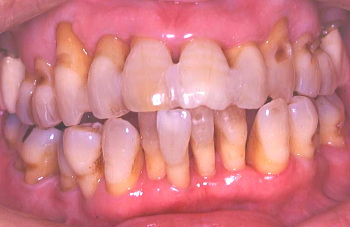

① 初診時の口腔内の状態:歯と歯の間に黒い歯石が見られ、歯肉は腫れている。

② 患者の熱心な歯磨きと医師や衛生士の機械的な歯のクリーニング(PMTC)により、 歯肉は艶を取り戻した。